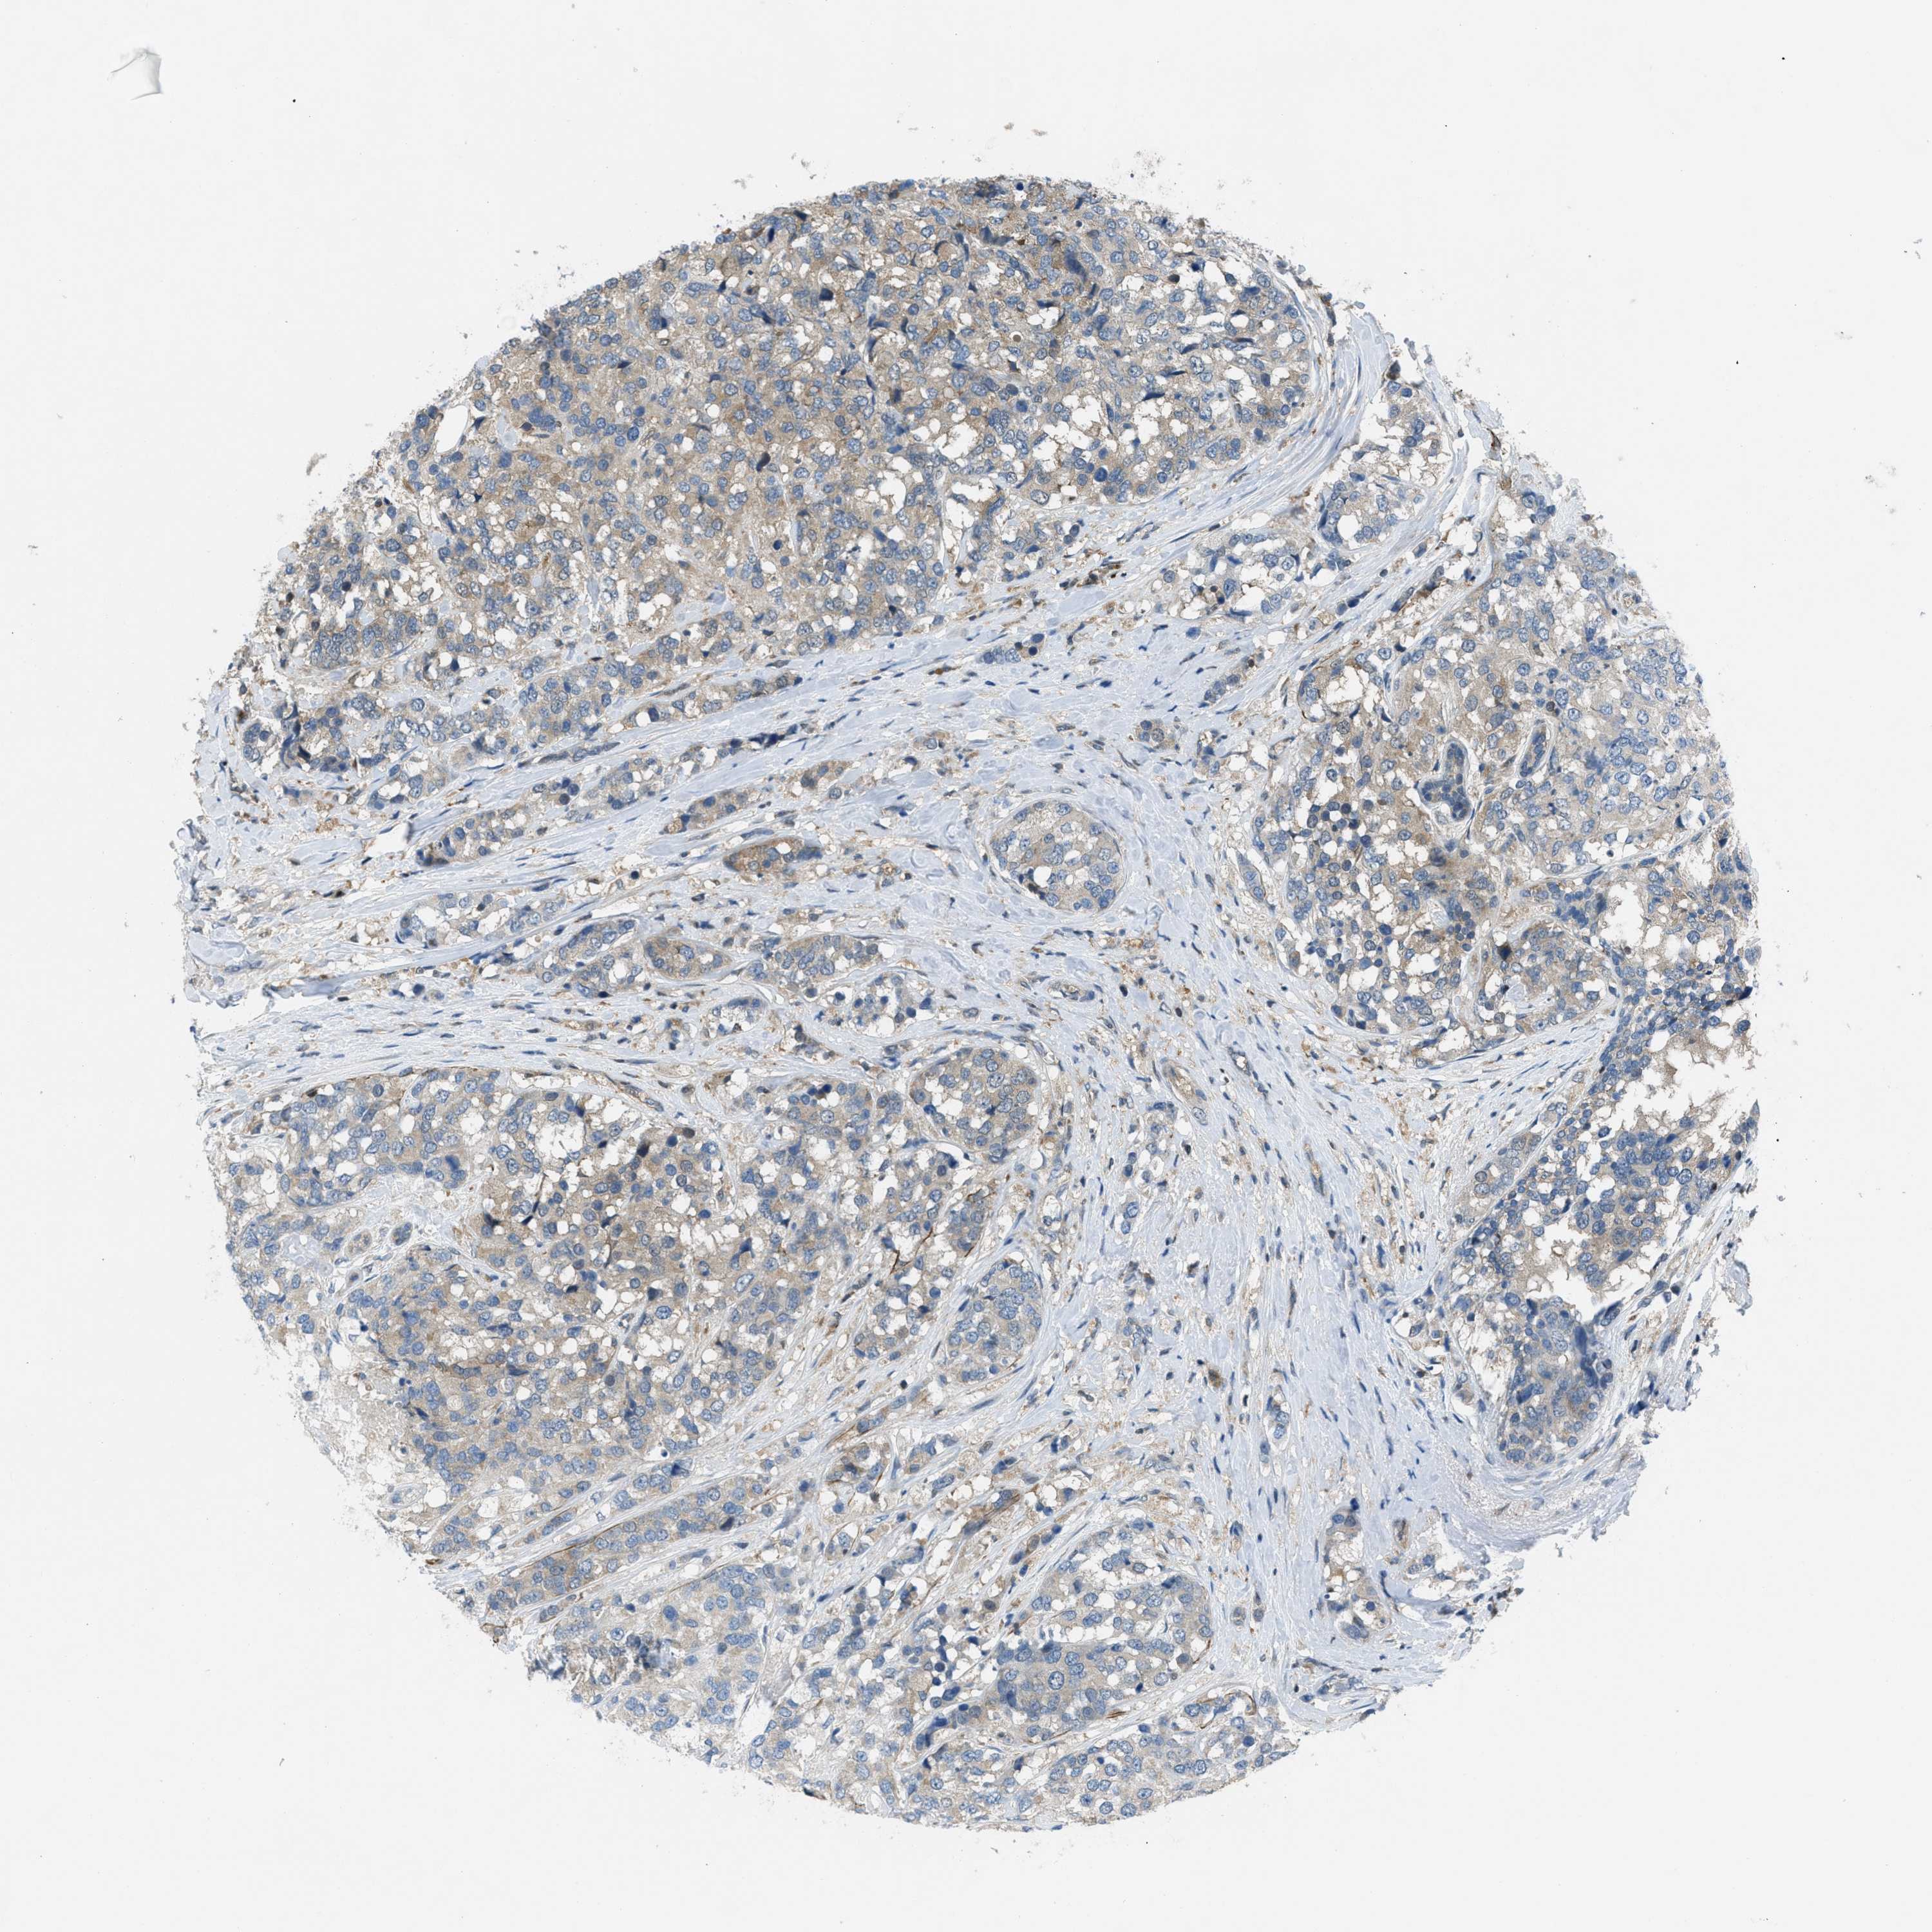

CANCER BREAST CANCER Show tissue menu

BRCA TCGA BRCA VALIDATION PROTEIN EXPRESSION